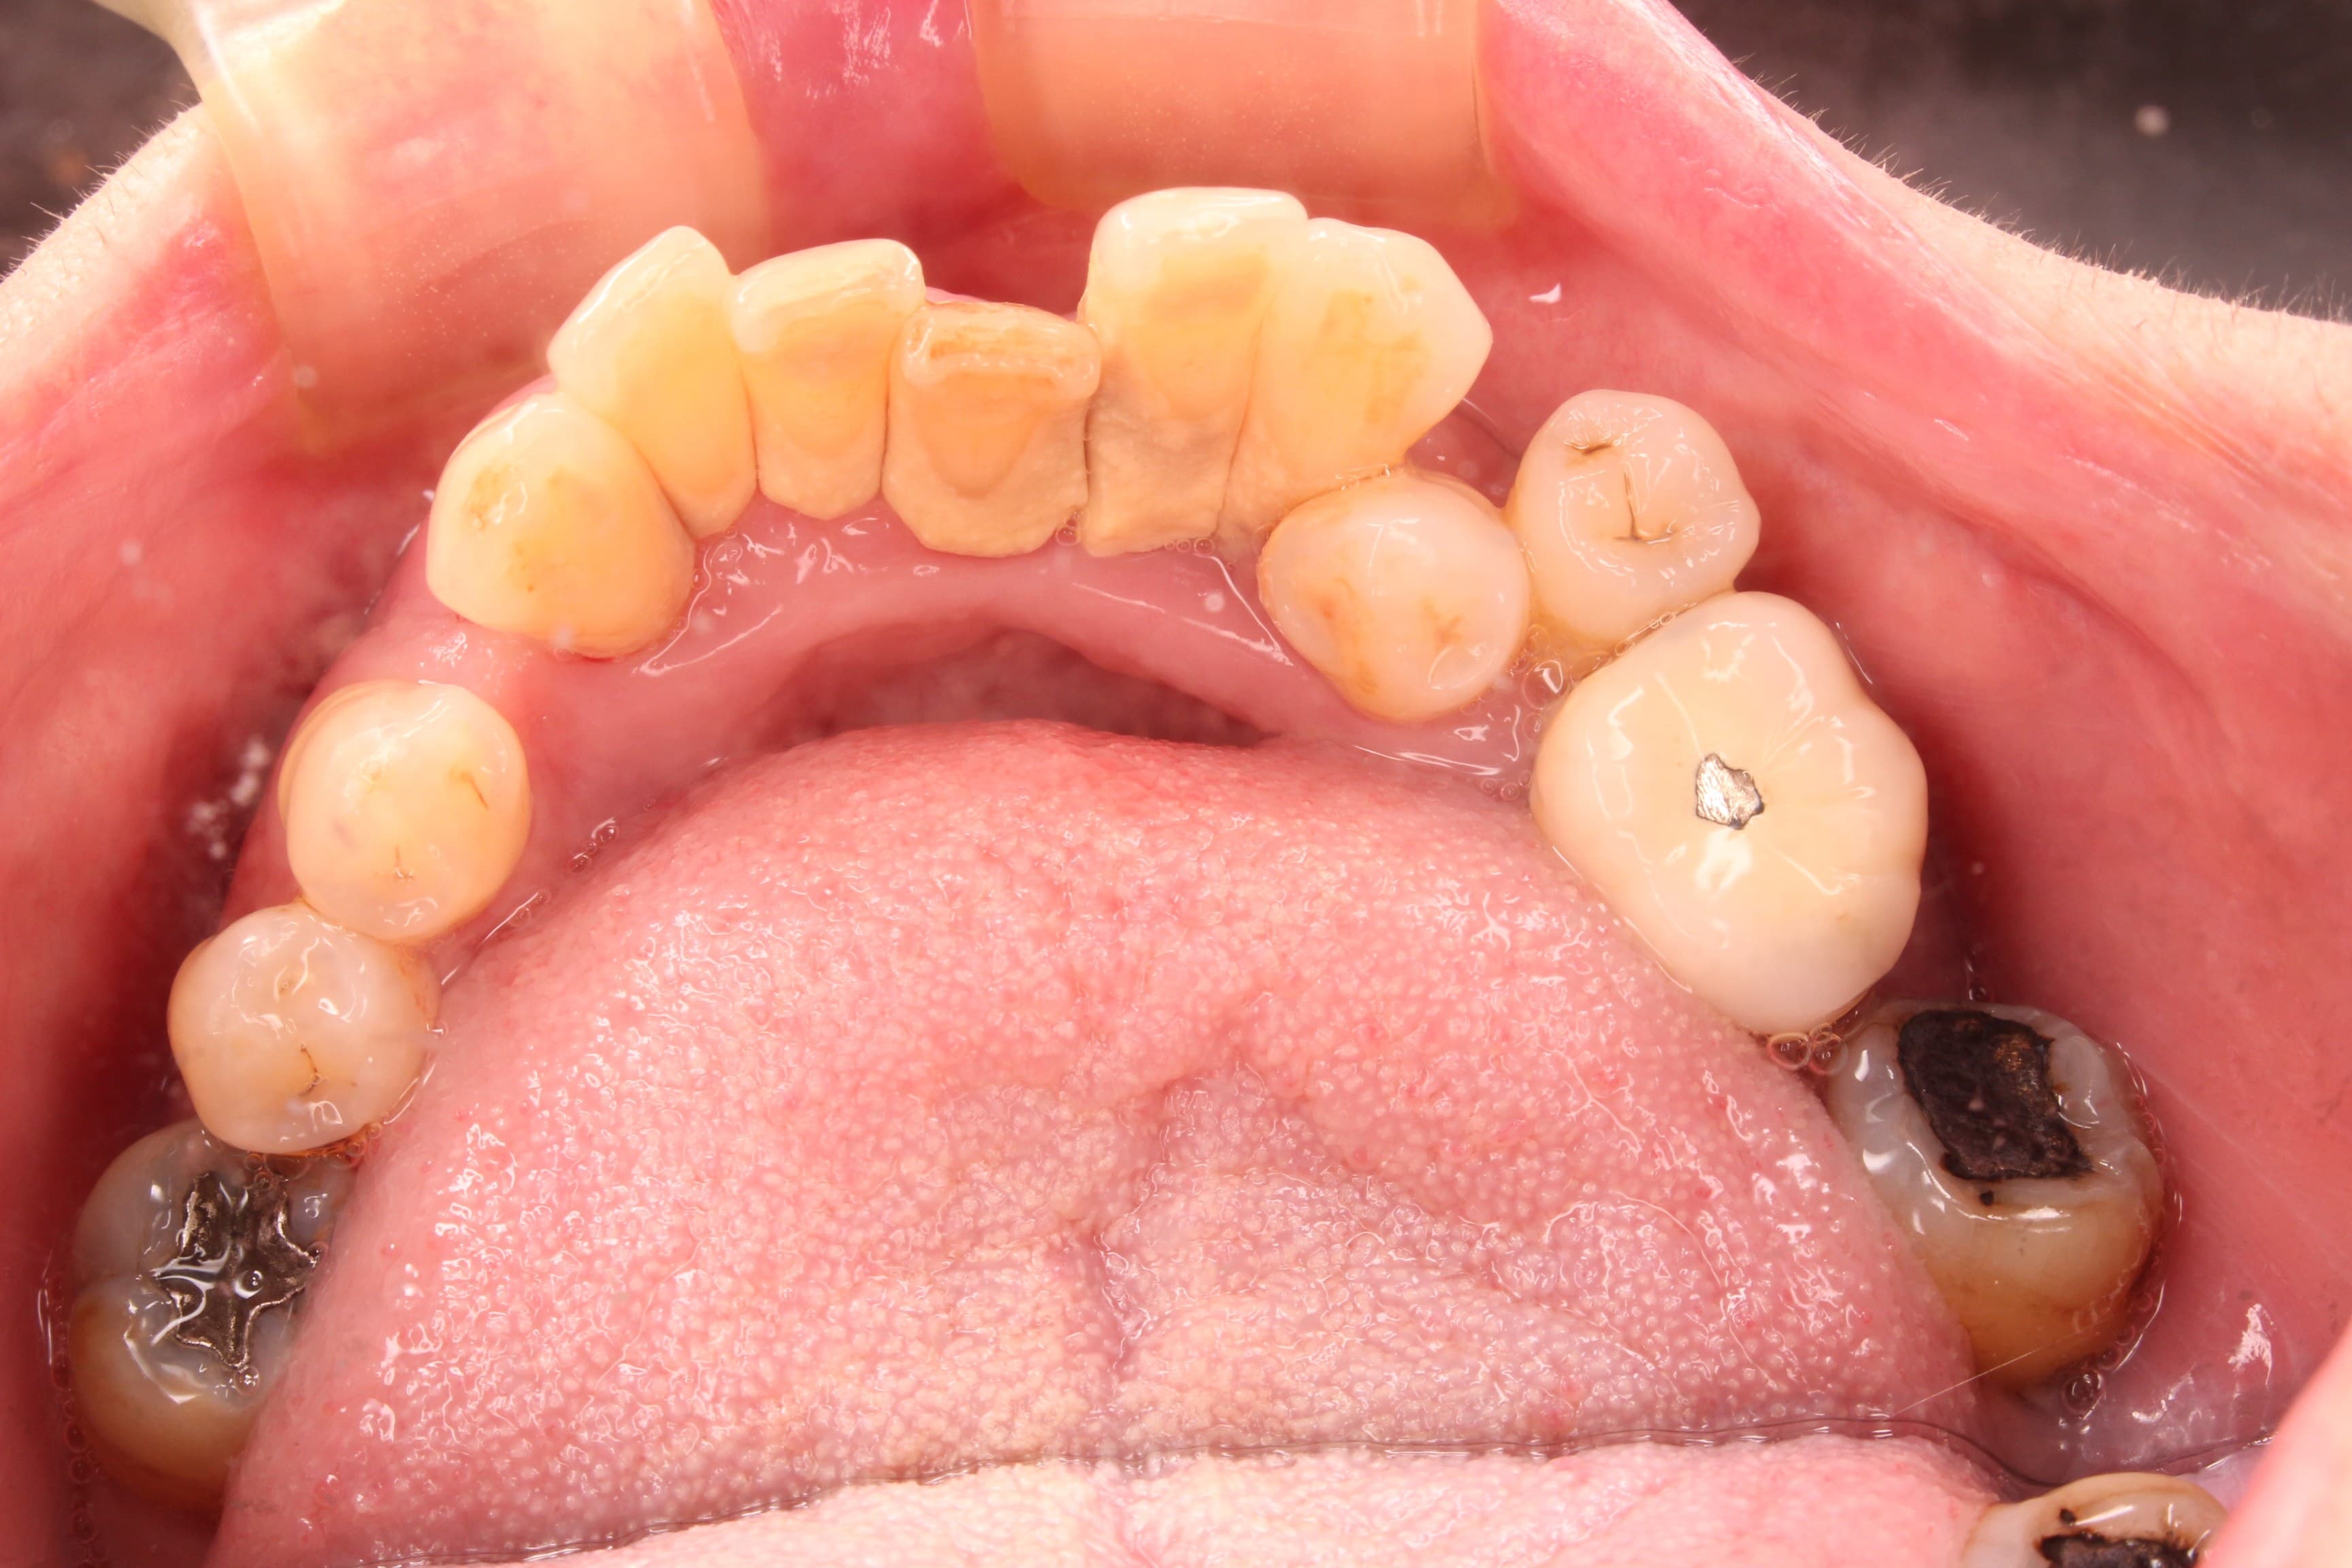

術前

術後

歯肉にのっているだけの歯の動きを完全に止める事は出来ませんが、治療後は日常の不便も無く、生活を送れるとのことでした。

可能な限り、現状維持が長く続くよう1か月に1度のメインテナンス管理を行っていきましょう!